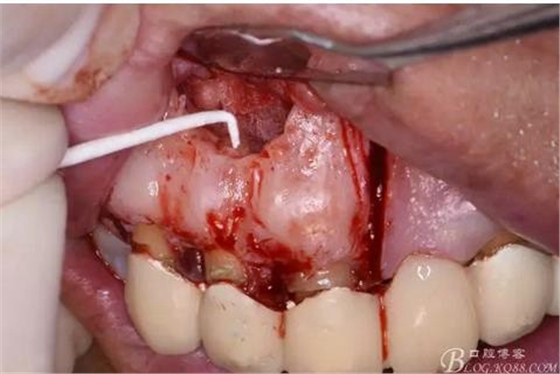

圖12.超生骨刀切除12根尖

圖13.根尖倒預(yù)備

圖14.吸潮紙尖干燥根管